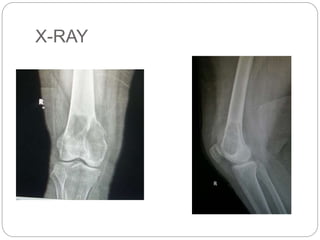

This document discusses 8 oncology cases. Case 1 involves a 40-year old female with right knee pain. Case 2 is a 28-year old male with a left subtrochantric fracture from a MVA who is now experiencing increasing left knee pain and swelling. Biopsy results showed high-grade osteosarcoma. Case 3 is a 30-year old female with breast cancer and bone metastases causing bilateral hip pain.